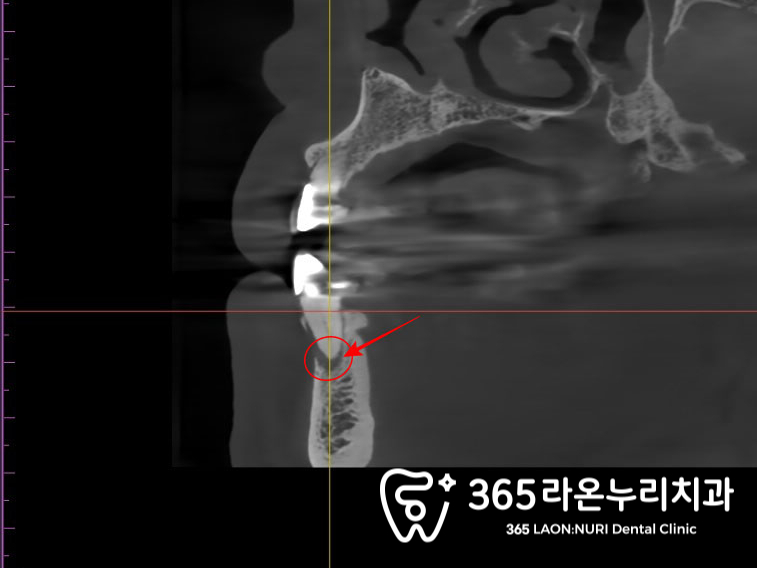

치근단 병소(Periapical lesion)는

치아 뿌리 끝(치근단) 주변에 생기는

염증성 병변을 말합니다.

주로 치수(신경) 감염이 근관을 통해

뿌리 끝까지 진행되면서 발생하며,

염증이 치조골로 확산되어 뼈가 소실됩니다.

치근단 병소는 급성과 만성

모두로 나타날 수 있으며,

급성의 경우 심한 통증과 고름이 동반될 수 있습니다.